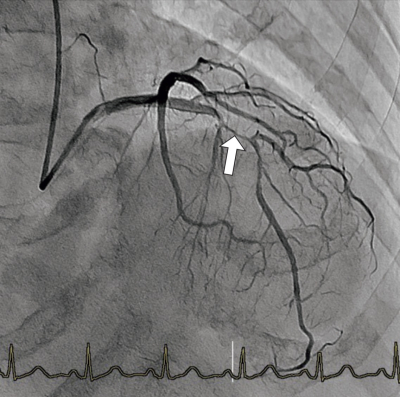

冠動脈造影検査が施行された。冠動脈造影像別に示す。矢印で示す血管はどれか。

a. 左冠動脈前下行枝

b. 左冠動脈主幹部

c. 左冠動脈回旋枝

d. 右冠動脈

e. 中隔枝